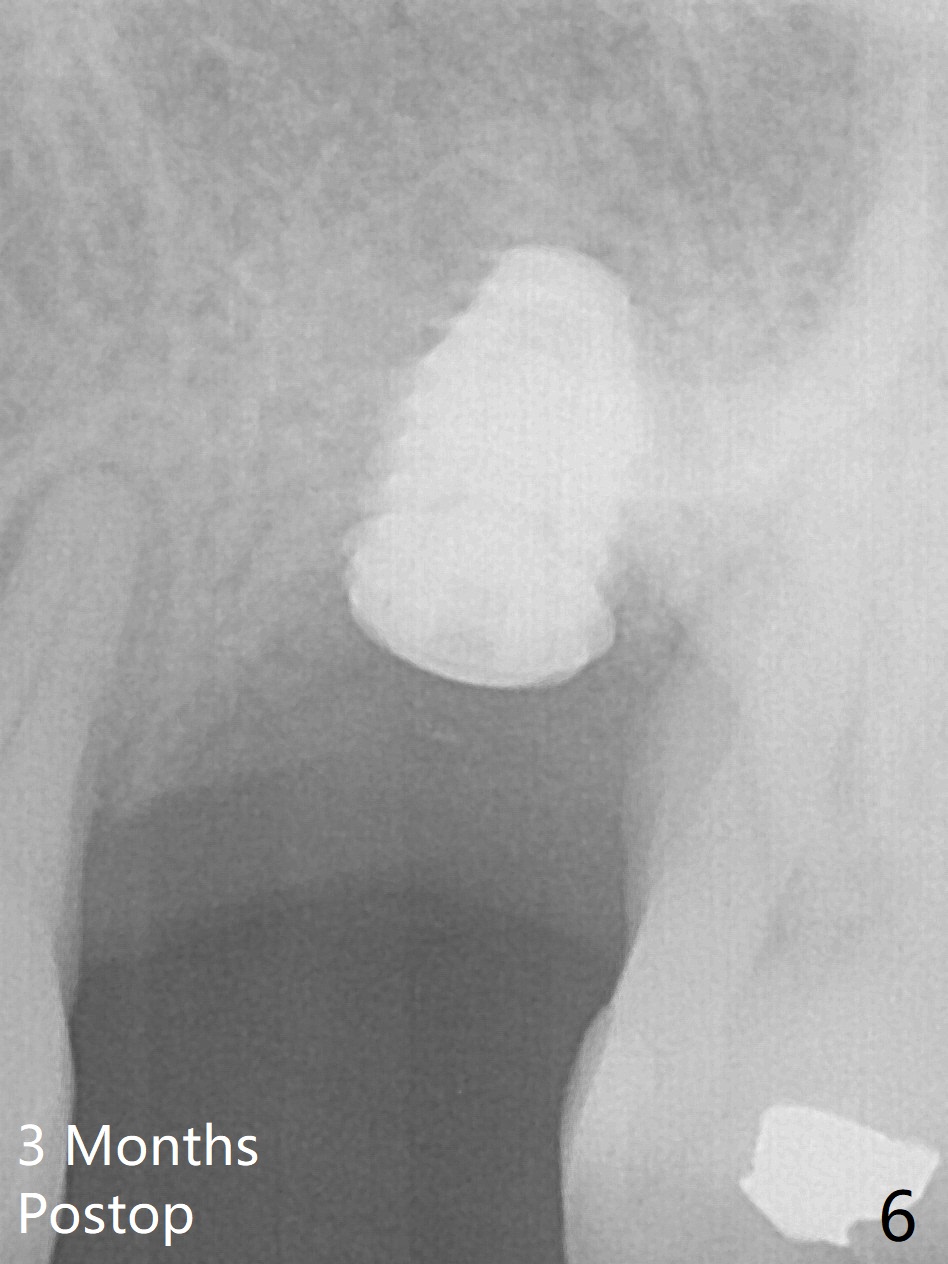

When an IBS implant with PAT surface (4.5x9 mm at #14; Fig.1 CT coronal section with ~ 7 mm bone height) is uncovered nearly 12 months postop, it is loose with a peri-implant space. Immediately post its removal and debridement, an IS dummy implant with SLA surface treatment (Fig.2: 4.5x10 mm) is placed. When a definitive implant is placed (Fig.3,4: 5x7.3 mm), it is subcrestal buccally and nearly equicrestal palatal. The remaining periimplant space is to be filled with demineralized cortical allograft. PAT: photo activated treatment (particles of calcium phosphate and a heating treatment). There is no apparent bone loss 3 months postop (Fig.5,6). The implant is uncovered with placement of a 5.7x4(4) mm cementation abutment and a nonfunctional provisional.